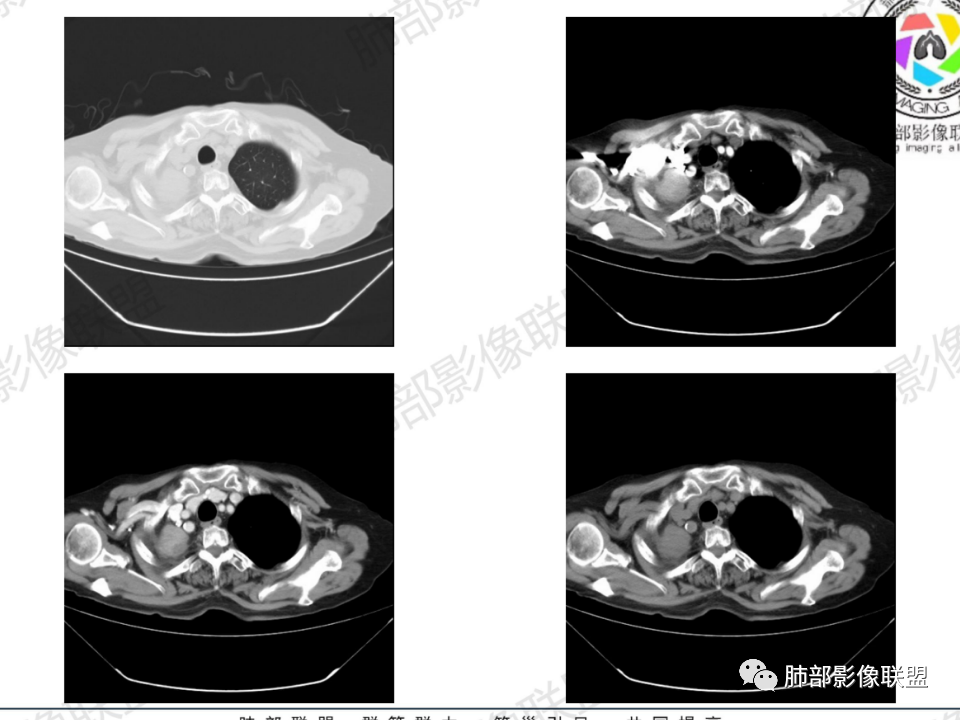

临床信息:老年女性,亚急性病程,咳嗽发热。有激素使用史。既往有淋巴结结核病史。肿瘤标记物Ca125升高。血沉升高,C反应蛋白轻度异常。 影像所见:右侧胸廓相对狭小,右肺上叶不规则团块影贴附纵隔旁,轻度分叶,整体密度较均匀,偶见钙点。

相应上叶尖端及前段支气管开口未能追踪(阻塞),开口处见钙化。病灶渐进性强化,并衬托出较完整尖段及前段含液支气管影。支气管开口区域未见异常高密度强化(如类癌等)及相对乏血供区(如鳞癌)。病灶区未见液化坏死。右上纵隔及胸廓入口区未见病灶胸膜外突破(栽赃)。

纵隔及双肺门见钙化淋巴结。心包积液,右侧胸腔积液(提示存在活动新病灶)。双侧胸膜下见多发斑点状钙化,胸廓变形(提示存在结核基础病变可能)。 诊断意见:综上,右肺上叶块状影更符合继发性肺结核。 最后小结:既往诊断淋巴结结核,提示已治愈。近2年服用激素,可疑诱导结核复燃,也可引起发热。纵隔肺门淋巴结肿大钙化,压迫支气管,右肺上中下叶支气管均狭窄,所以引起喘息咳嗽。尖段支气管受累闭塞,导致肺不张、支气管粘液栓,出现条状无强化区。病变累及胸膜,导致结核性胸膜炎并胸水,引起右侧胸痛。实验室检查血沉快,CA125高,低蛋白,均符合结核。下一步,建议支气管镜尖段支气管刷检并抗酸染色。(本段摘自於雄老师精彩发言)